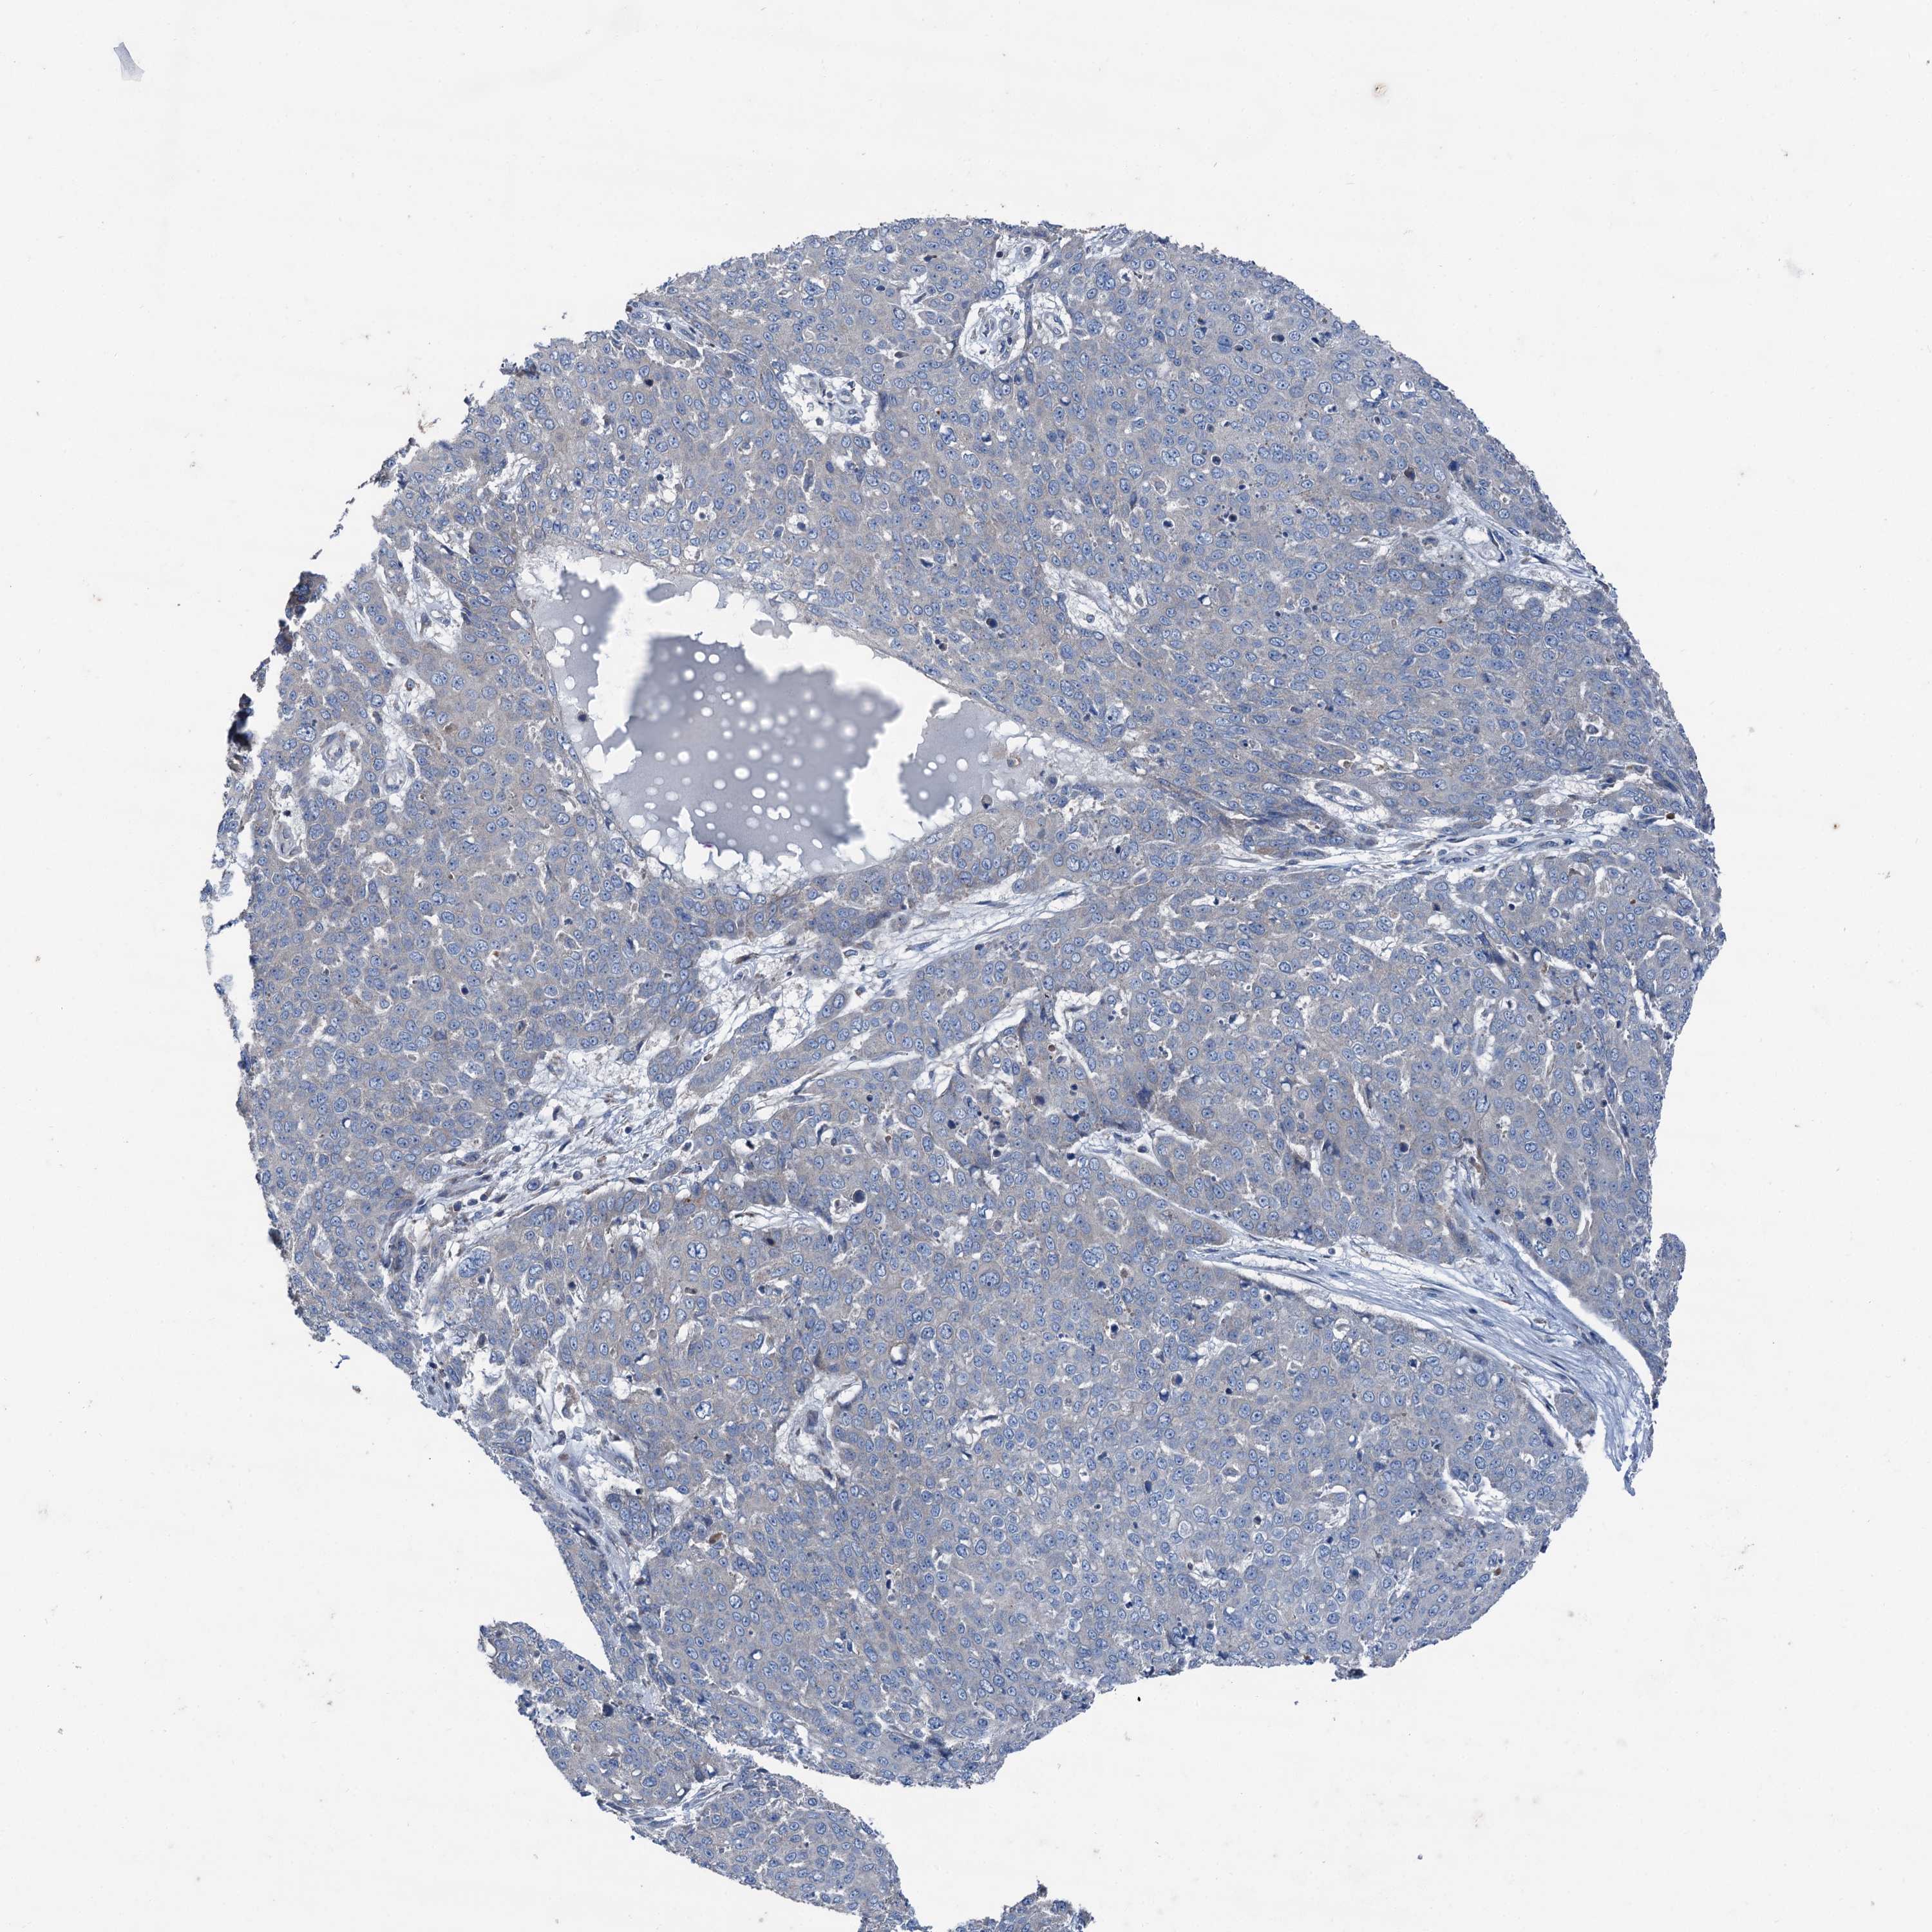

SKIN CANCER - Protein expressioni

A mouse-over function shows sample information and annotation data. Click on an image to view it in a full screen mode. Samples can be filtered based on level of antibody staining by selecting one or several of the following categories: high, medium, low and not detected. The assay and annotation is described here.

Antibody stainingi

Antibody staining in the annotated cell types in the current human tissue is reported as not detected, low, medium, or high, based on conventional immunohistochemistry profiling in selected tissues. This score is based on the combination of the staining intensity and fraction of stained cells.

Each image is clickable and will lead to virtual microscopy that enables deeper exploration of all samples and also displays staining intensity scores, fraction scores and subcellular localization as well as patient and tissue information for each sample.

Antibody HPA038804

Basal cell carcinoma